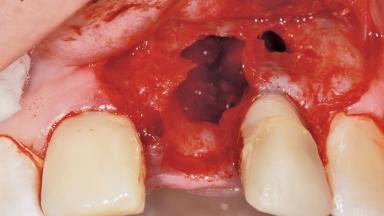

Late Placement of an Implant in a Maxillary Left Central Incisor Site

A 36-year-old female patient was referred for the replacement of the upper left central incisor (tooth 21), which had fractured. Although the tooth had been asymptomatic for many years, the crown began to loosen, at which time she presented to her dentist for an assessment. Teeth 21 and 22 had both been endodontically treated many years previously. She was a healthy individual and a non-smoker.

Bone Volume Horizontally and vertically sufficient Horizontally deficient Deficient vertically or deficient vertically AND horizontally

Bone Volume Deficient horizontally, requiring prior grafting